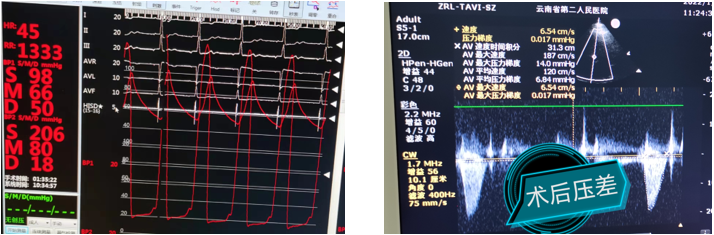

术后即刻评估

术后压差从108mmHg降至6.84mmHg,无瓣周漏,瓣膜正常工作,血流动力学即刻得到改善。